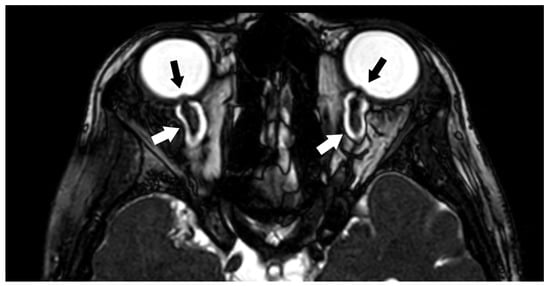

3.1.2. Optic Nerve (II) and Orbital Masses

3.1.3. Ocular Motor Nerves (III–IV–VI)